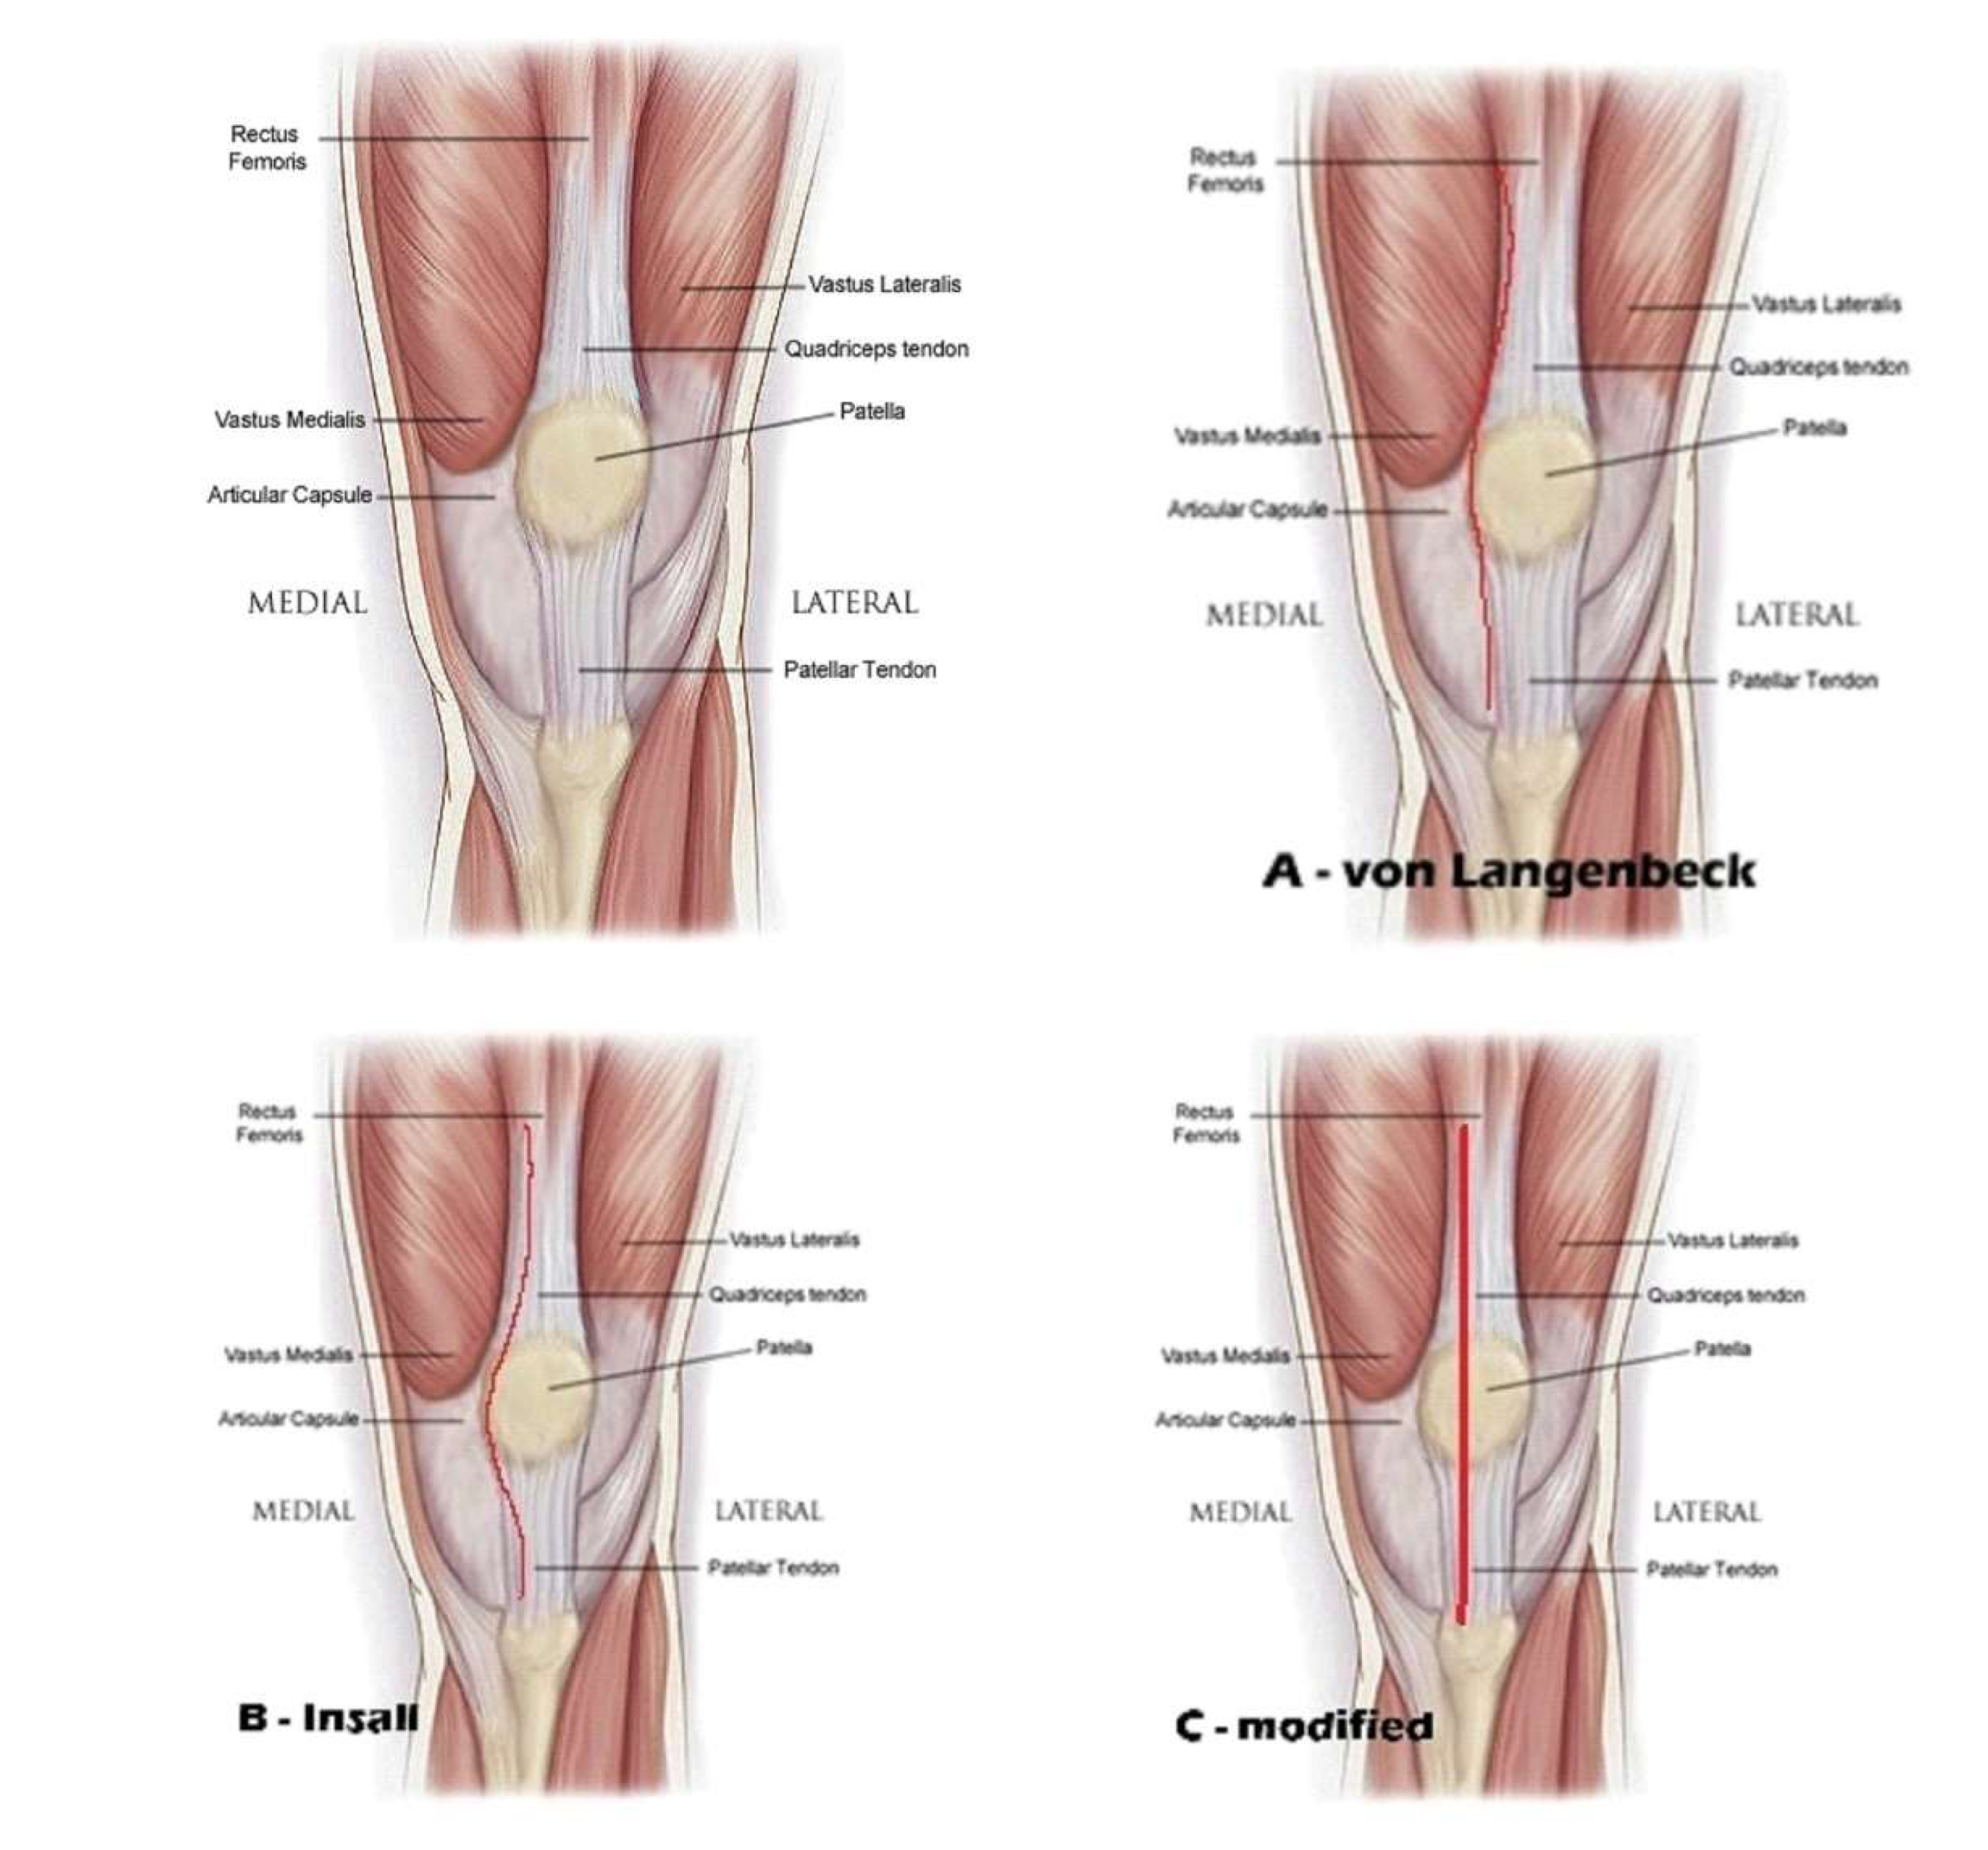

Despite von Langenbeck's 1878 description, there is still debate regarding the best surgical technique for TKA. Von Langenbeck described the approach followed the medial border of the quadriceps tendon, and left a cuff of tissue on the patella on which to repair the medial joint capsule [1]. Criticism of this approach included disruption of the quadriceps mechanism at the junction of vastus medialis and the quadriceps tendon, later destabilizing the patella.

In 1971, Insall described a variation of this method that involved cutting the quadriceps tendon at the point where the medial third and lateral two-thirds meet [2]. However, the cut went along the patella's medial border, obstructing the cuff that would be used for repair.

We modified this medial approach, by making an incision at the internal border of the quadriceps tendon leaving 3-4 mm on internal side, peeling from patella almost half of fibrous - tendinous part and continue on the patella tendon leaving 3-4 mm on internal side. We repair the medial joint capsule and the continuity of the extensor mechanism by two or three bone tunnels on the patella to reinsert the tendinous peeling from the patella, we name this - transtendinous approach of the extensor mechanism in TKA.

Figure 1. Medial parapatellar arthrotomy A - von Langebeck B – Insall C - modified.